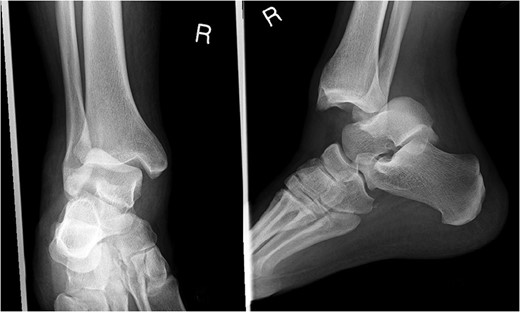

A 30-year-old male patient presented to Emergency Department (ED) following a run over injury. The patient described the mechanism of injury as moving his body over his run over foot. On clinical examination, there was obvious deformity and swelling of the right ankle. Dorsalis pedis pulse was felt but weak compared to the contralateral side with a capillary refill time under 3 s. The posterior tibial artery could not be palpated because of the deformity. X-rays showed posterior ankle dislocation without associated fractures (Fig. 1). Urgent reduction of the dislocation was done under sedation in ED. The knee was first flexed to relax the tendon Achilles then longitudinal traction with gentle forward force applied to the heel with immediate reduction of the deformity achieved. The foot was reassessed for vascular status. Triphasic pulse in both drosalis pedis and posterior tibial artery was detected with hand held Doppler. Ankle was immobilized in posterior below knee back slab to accommodate for swelling and check x-rays confirmed reduction of the ankle joint (Fig. 2). CT scan was done afterwards to define any subtle incongruity or osteochondral fragments entrapped in the joint. CT did not show any associated fractures and showed congruent reduction of the ankle joint (Fig. 3). Patient was mobilized touch weight bearing for first 2 weeks. The back slab was changed for weight bearing short leg cast and progressive weight bearing was allowed for the following 4 weeks. At 6 weeks follow up, plaster was removed and on examination patient still had moderate tenderness over the medial joint line and deltoid ligament area. Also, patient had limited range of plantar and dorsal flexion. Referral for physiotherapy was done for start of functional rehabilitation and range of motion exercises and in mean time MRI was done to delineate extent of ligamentous injury. MRI showed bone bruising of the lateral malleolus, medial malleolus and lateral talus (Fig. 4). The anterior talufibular ligament (ATFL), calcaneofibular ligament (CFL), posterior talofibular ligament (PTFL) and deltoid ligaments were sprained but intact. At 12 weeks follow up, patient could walk normally without any symptoms of instability and achieved 20° of both plantar and dorsal flexion. At 16 weeks, patient achieved full range of motion of ankle and was able to return to work. At 24 weeks follow up patient was able to resume his sport activates as preinjury level.

Plain film X-rays of right ankle showing total posterior dislocation of the ankle joint with no fracture of the medial or lateral malleolus.

Post reduction films showing adequate reduction of the ankle joint with no talar shift or syndesmotic injury.